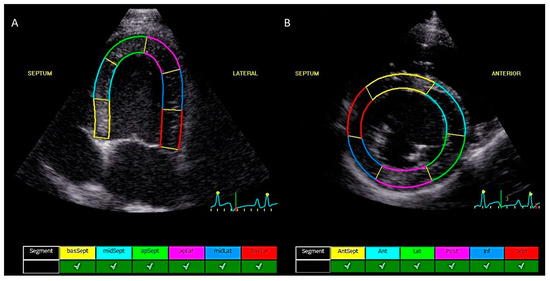

2.2. Echocardiographic Measurements